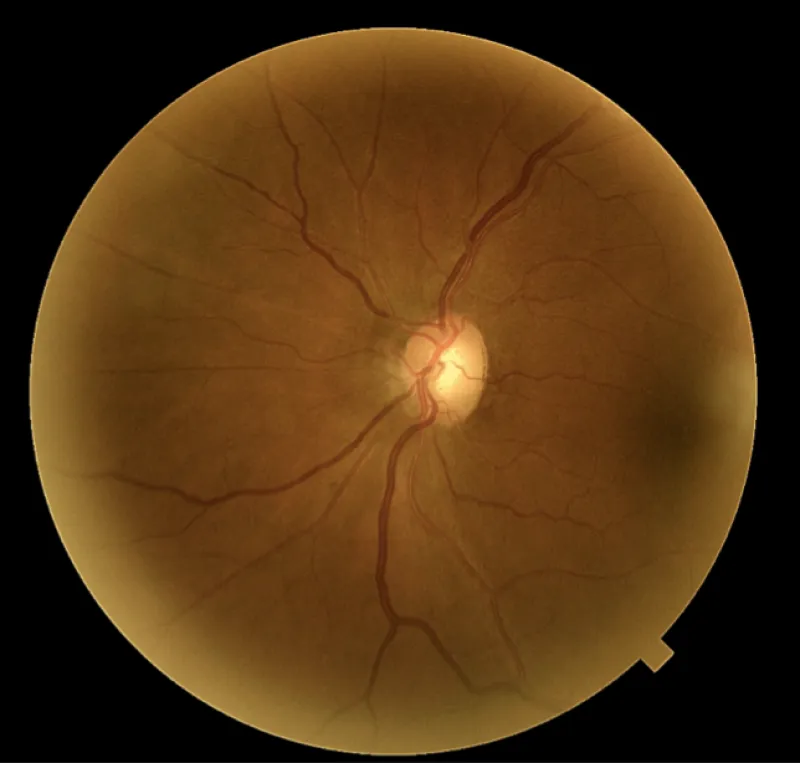

Les mesures de pression intraoculaire du patient, prises avec l'OCT Solix ont varié de 22 mmHg à 29 mmHg au cours des trois dernières années avec une PIO maximale de 25 mmHg OD et 29 mmHg OS. La pachymétrie est mesuré à 513 µm OD et 514 µm OS. Ses têtes de nerf optique étaient roses et distinctes avec des rapports C/D mesurant .55V/.50H OD et .65V/.55H OS. Un examen OCT-A a été réalisée sur le Solix pour évaluer davantage la présence de glaucome par rapport à l'hypertension oculaire.